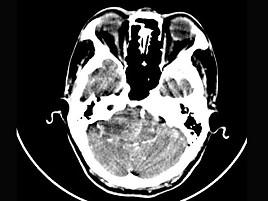

女,45岁,右耳听力下降半年余,CT检查如图,最可能诊断为 ( )

• A.脑膜瘤

• B.继发性胆脂瘤

• C.三叉神经瘤

• D.原发性胆脂瘤

• E.听神经瘤

答案: E